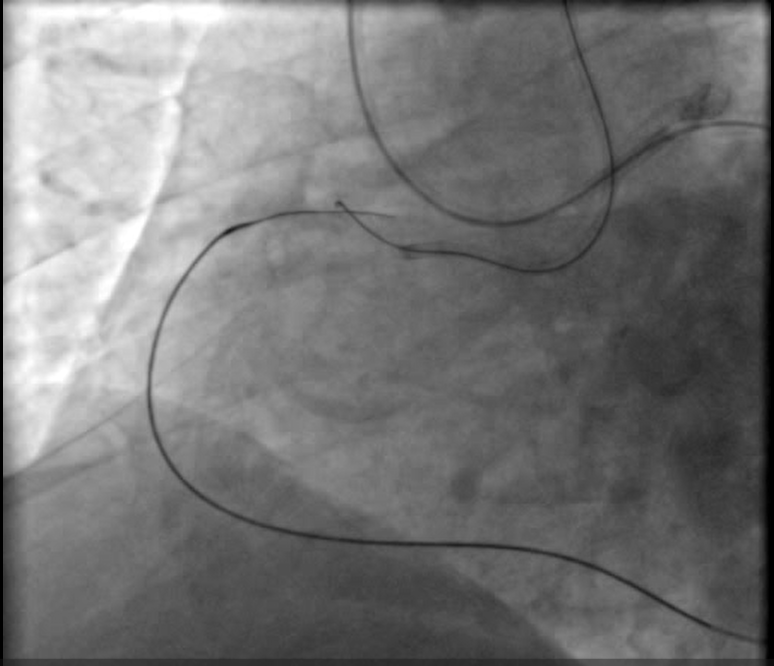

Dual femoral access , Dual injection through AL1 7F & XB4 7F Target vessel assessment ( RCA ) with calculation of J-CTO score then deciding which strategy we decided a Trial antegrade, If failed , Retrograde through septals , If failed , shift to epicardial collateral.Antegrade Trial with GAIA Wires , Corsair MC failed , Retrograde trial through septals failed as it seems not connected shifting strategy to epicardial : Sion blue navigated through epicardial collaterals , corsair 150 MC successfully passed through PL branch MC advanced to distal Cap & GAIA 2nd wire successfully pierced distal cap , but failed to entre antegrade guide Trial snaring through AL guiding by a home made snare but failed , Guiding changed to JR with successful snaring of wire into antegrade guide followed by MCPilot 50 wire introduced through retrograde MC ( Rendezvous Technique , Reverse TIP IN ) then MC Withdrawn we started conventional PCI with Antegrade Balloon dilatation 2.5 * 15 mm semicompliant then 3.5 * 15 mm NC balloons Then stenting with 2 overlapping DES with postdialtation with 4*15 NC balloon with final good angiographic results